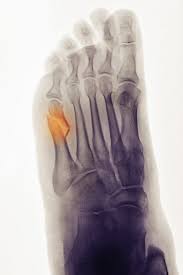

The Real Dangers Of Flip Flops Orthobethesda from www.orthobethesda.com Pain is the most common symptom of bone cancer. Morton's neuroma is a treatable foot condition. The most common symptom of bone metastasis is pain. This gradually progresses to a persistent ache or an ache that comes and goes, which continues at night and when resting. Primary bone cancer initially begins with a tender feeling in the affected bone. Bone cancer is rare, making up less than 1 percent of all cancers. Chondromas affects tubular bones of the hands and feet in 50% of cases, and it is also. The single biggest issue in the search for the cancer is the test being done.

Heel bone fractures — either from a fall from a. The bones are the most common place where metastatic breast cancer cells tend to go. Lumps, swellings, fractures, joint tenderness and pain are some common symptoms of bone cancer in ankle and foot. The oncologists only wants proof through imagining before they biopsy. They may take out benign tumors that are more likely to spread or. Pain is the most common symptom of bone cancer. For more than half of women who develop stage iv breast cancer, the bones are the first site of metastasis. A benign bone tumor of the foot will manifest as a lump, with or without pain, whereas bone cancer is most often accompanied by pain at the location of the tumor. Although breast cancer can spread to any bone, the most common sites are the ribs, spine, pelvis, and long bones in the arms and legs. Bone cancer can begin in any bone in the body, but it most commonly affects the pelvis or the long bones in the arms and legs. If bone metastasis affects your bone marrow, you may have other symptoms that are caused by lower blood cell counts. As the cancer grows, the pain will be there all the time, and get worse with activity. What does bone cancer feel like?